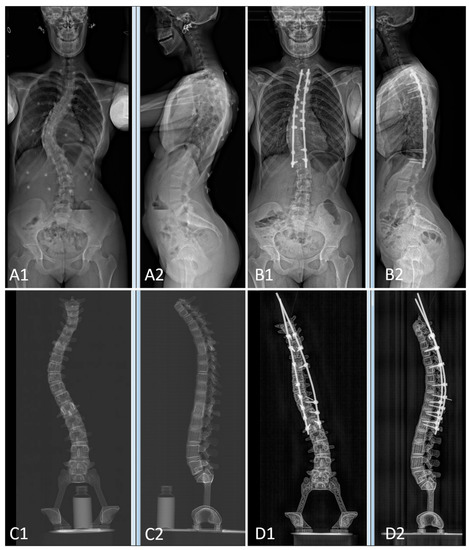

The pre- and postoperative constructs of one of the 3D-printed spine twins can be seen in Figure 9. Figure 8 (Patient 1) and Figure 10 (Patient 2) demonstrate pre- and postoperative bi-planar X-rays of the actual patient and their 3D-printed twin spine.

Figure 8. Bi-planar X-rays of patient 1 and 3D-printed twin 1. (A): Preoperative X-rays of patient 1 ((A1): frontal view, (A2): lateral view). (B): Postoperative X-rays of patient 1 ((B1): frontal view, (B2): lateral view). (C): Preoperative X-rays of 3D-printed twin 1 ((C1): frontal view, (C2): lateral view). (D): Postoperative X-rays of 3D-printed twin 1 ((D1): frontal view, (D2): lateral view).